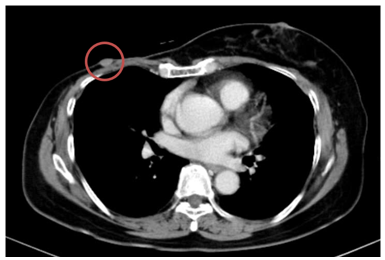

Ca lâm sàng: Điều trị đích bệnh nhân ung thư phổi không tế bào nhỏ giai đoạn muộn di căn nhiều cơ quan, tại Trung tâm Y học hạt nhân và Ung bướu – Bệnh viện Bạch Mai

Ung thư phổi là nguyên nhân hàng đầu gây tử vong do ung thư trên toàn thế giới. Trong đó, ung thư phổi không tế bào nhỏ (NSCLC) là thể thường gặp nhất, chiếm khoảng 85% các trường hợp [1]. Phần lớn bệnh nhân được chẩn đoán ở giai đoạn tiến...